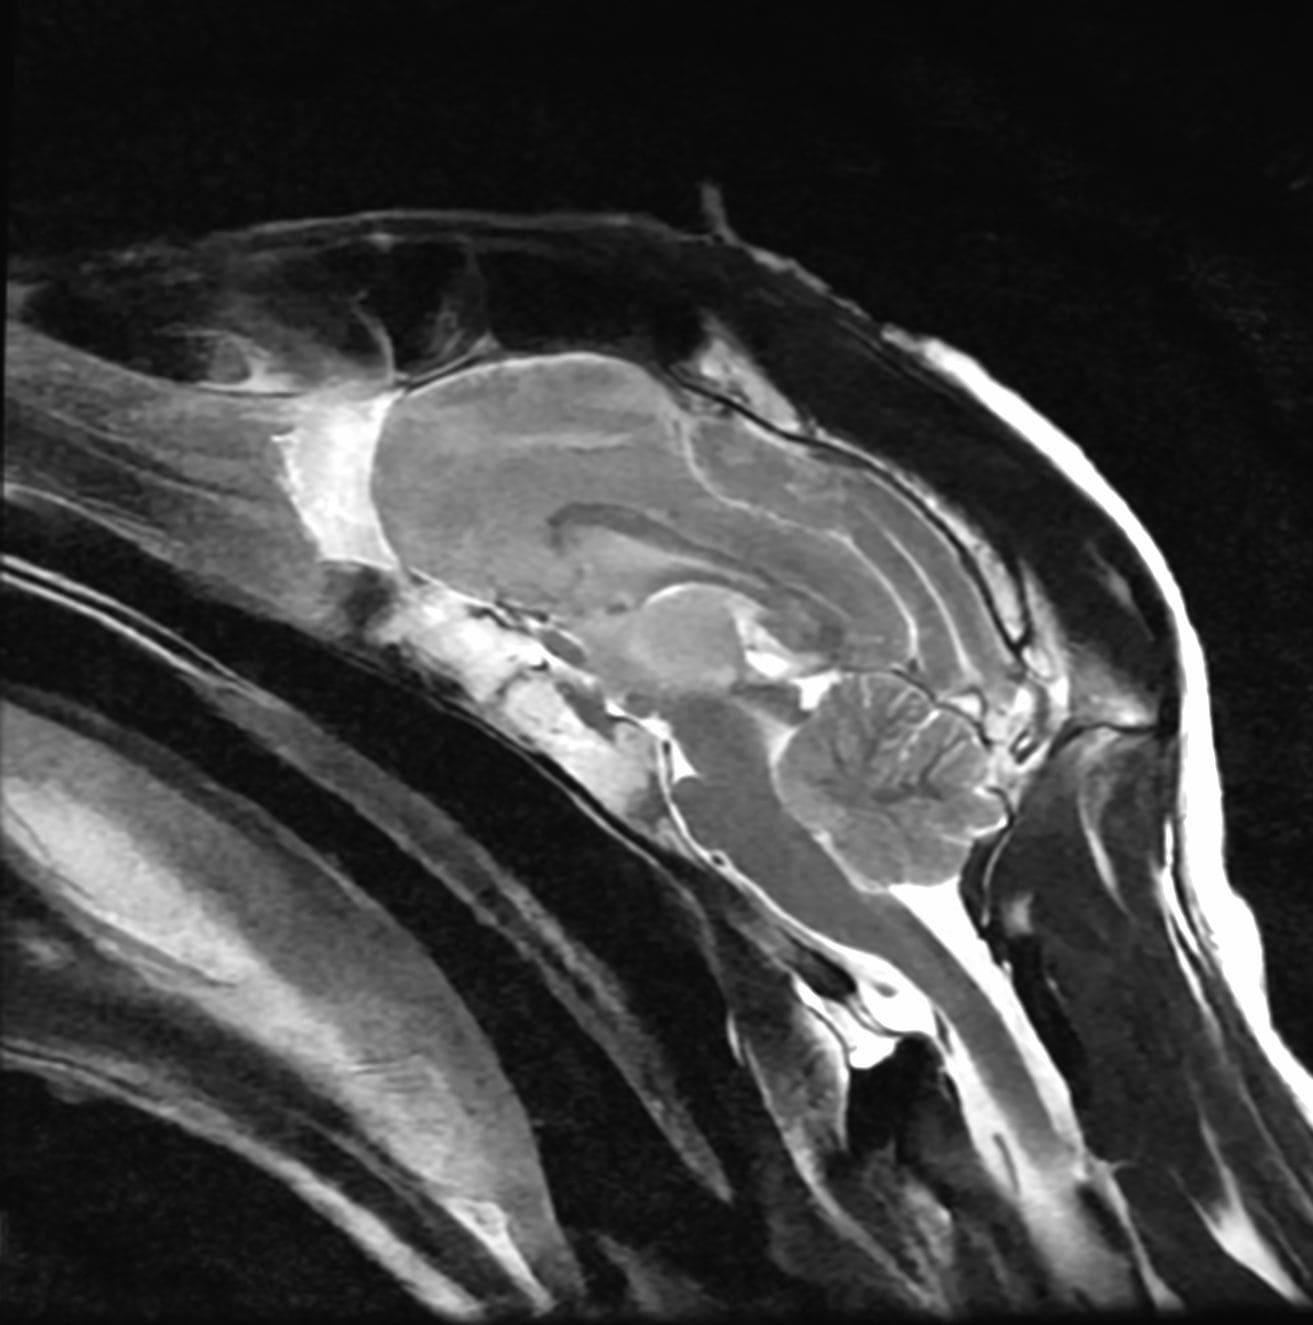

- Intelligent Reporting: Dedicated subspecialty radiologists for every scan, ensuring precise, clinically relevant, and actionable reports.

- Clinical Collaboration: A strong emphasis is on direct communication with clinicians and surgeons when required, with our radiologists readily available to discuss findings, clarify queries, and support clinical decision-making.